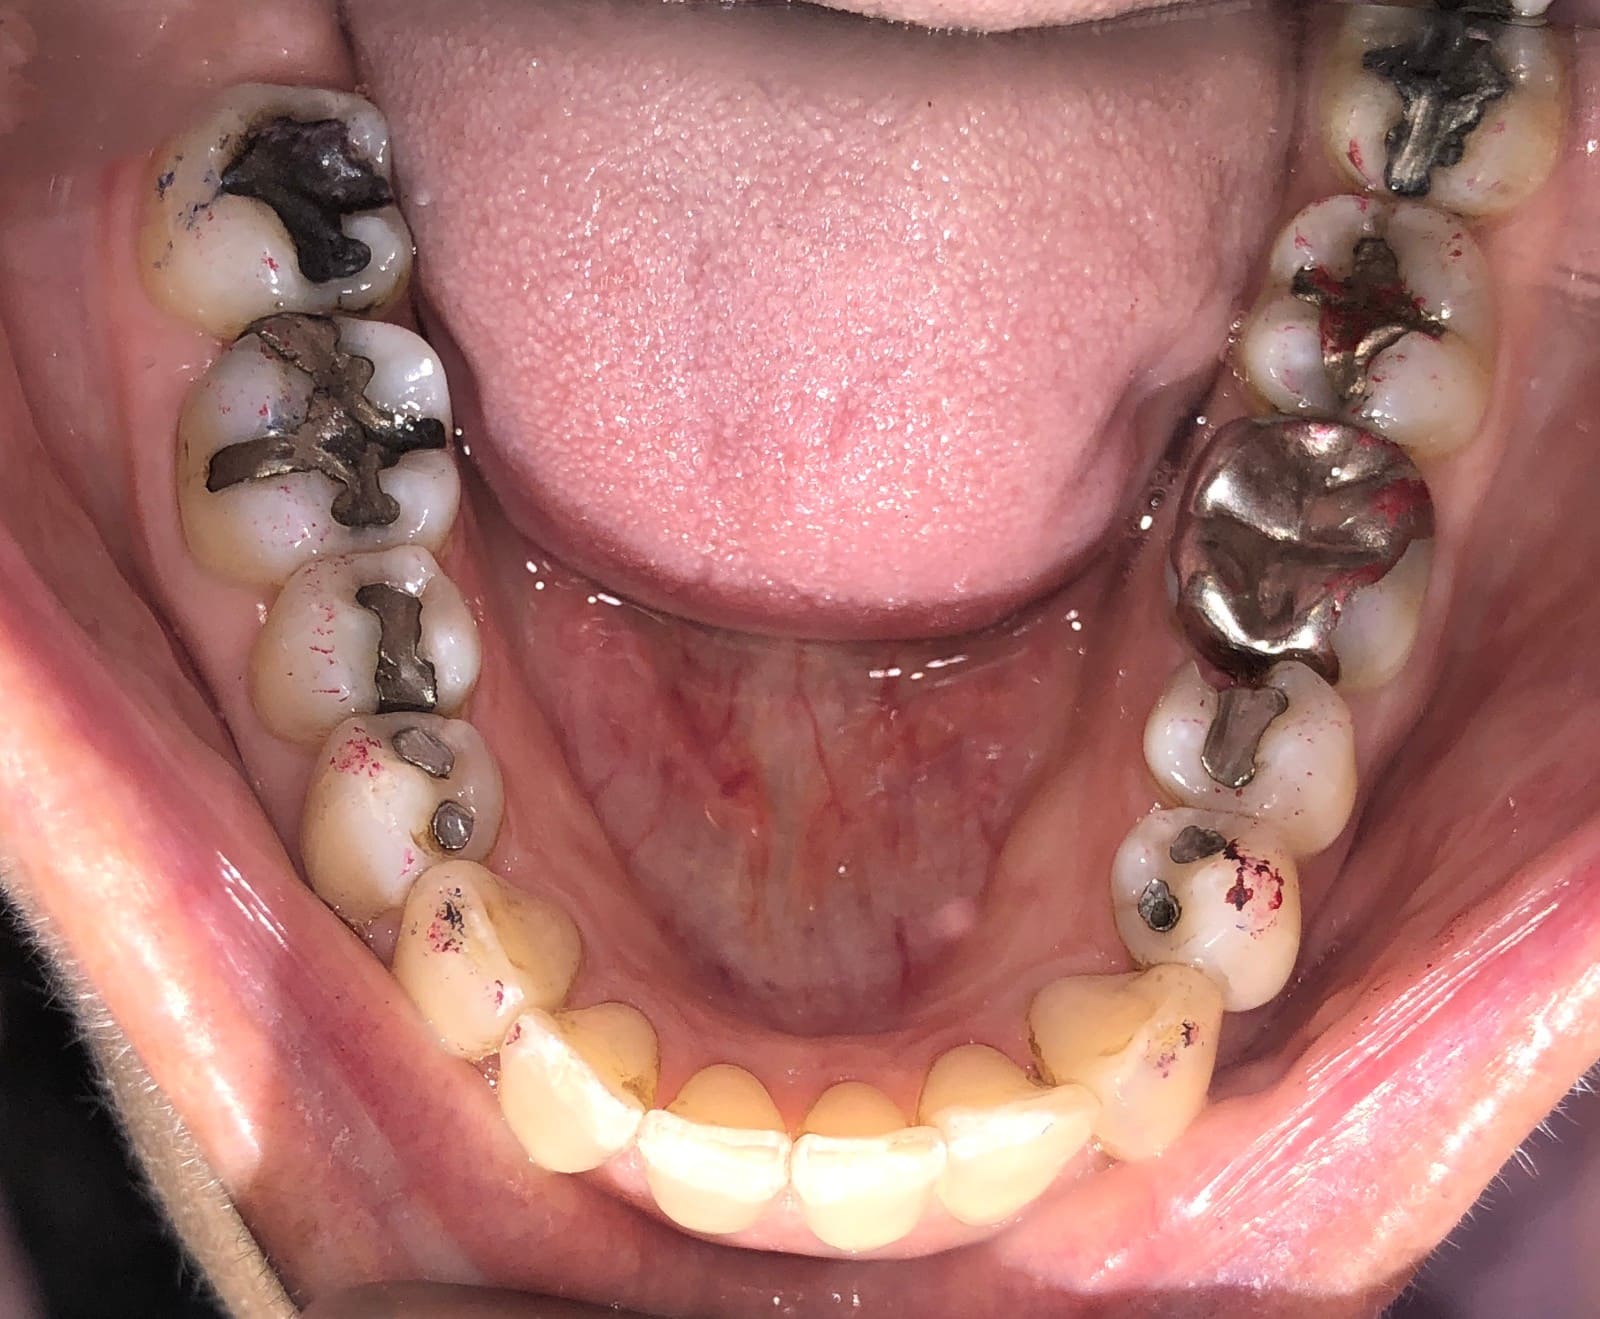

Initial